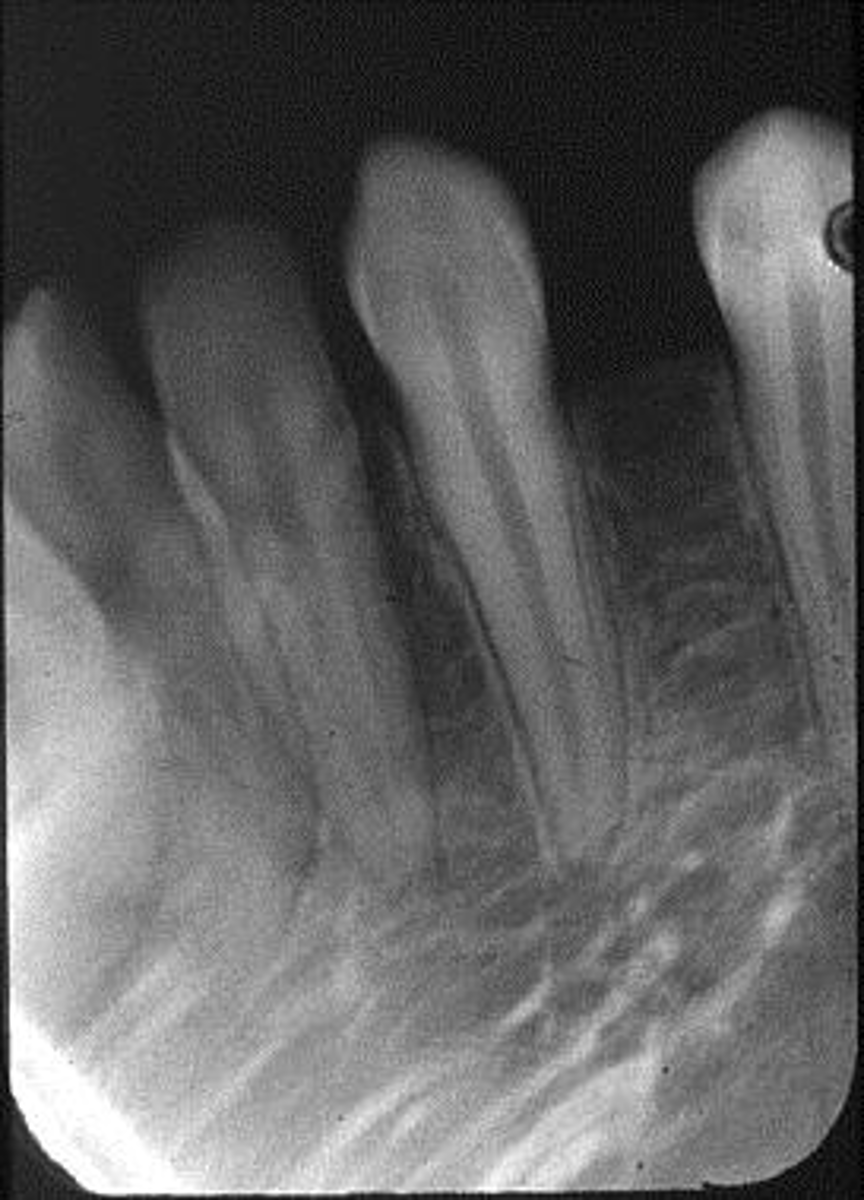

Elongated, vertical angulation, film holder (metal bar)

What is this error?